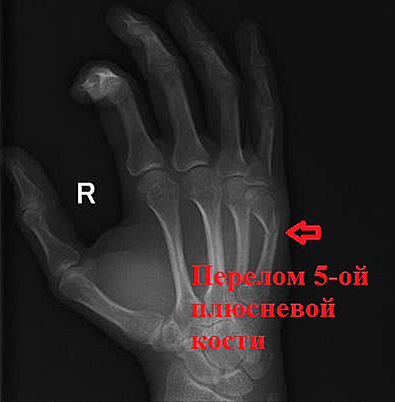

Пациент С. 23 года. травма при ударе кулаком о боксерскую грушу. Диагностирован типичный для этого вида травмы перелом 5 плюсневой кости.

В связи с неудовлетворительным положением отломков после репозиции было принято решение выполнить операцию.

Положение на отломков на контроле удовлетворительное.